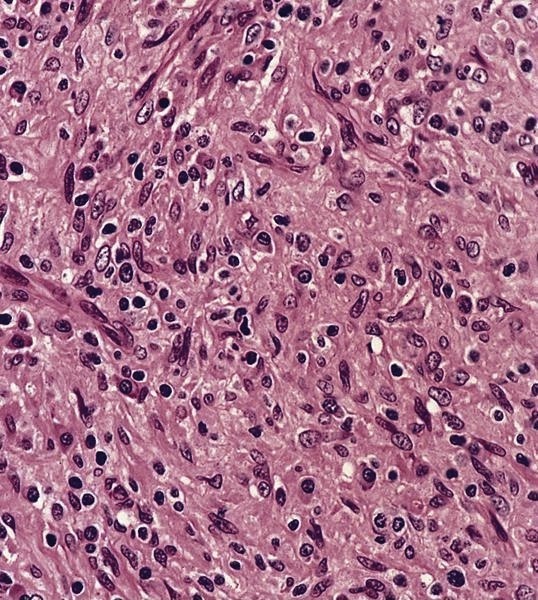

Microscopic (histologic) description

- Nodes show partial / complete effacement by storiform pattern of bland spindle cells, some with vacuoles

- Numerous vessels lined by plump endothelial cells, plasma cells and lymphocytes

- No multinucleated tumor cells, no foamy histiocytes

Microscopic (histologic) images

Contributed by AFIP and Chunyu Cai, M.D., Ph.D. (Case #532)

- Spindle cell proliferation resembling Kaposi sarcoma; no foamy histiocytes (Acta Cytol 1995;39:125)

- Kaposi sarcoma:

- Fascicular spindle cells, slit-like spaces, mitotic figures, no granular or acidophilic cytoplasm

- Spindle cells are CD31+ and CD34+

- S100- and CD68- (Am J Surg Pathol 1999;23:656)